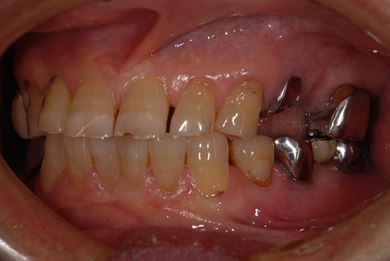

抜歯即日スピードインプラント治療+歯周外科治療

| 性別/年齢 | 男性 / 62歳 | ||||||||||||||||||||||||||||||||

| 主訴 | 左下の奥歯のブリッジがゆれて、痛みがある。 | ||||||||||||||||||||||||||||||||

| 治療方針 | 抜歯と同時にインプラント埋入を行い、治療期間を短縮する。 | ||||||||||||||||||||||||||||||||

| 治療内容 | インプラント2本(抜歯即日スピードインプラント)、ハイブリッドセラミッククラウン2本、歯周外科治療 | ||||||||||||||||||||||||||||||||